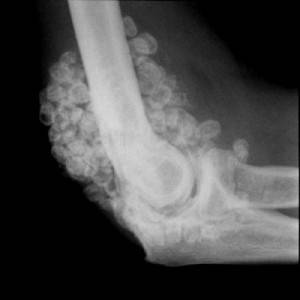

- синовиальный хондроматоз — формирование свободных хрящевых тканей;

Хондроматоз синовиальный

Это заболевание хрящевой ткани, когда нарушается процесс формирования хряща и в полости сустава образуются свободные хрящевые фрагменты. Развитие этой болезни начинается еще в детском возрасте, симптомами будут деформация костей и укорочение верхних и нижних конечностей.

Боль в локтевом суставе на фоне синовиального хондроматоза будет возникать при сгибании и разгибании руки. Со временем боль принимает постоянный характер, локтевой сустав отекает и становится тугоподвижным.

Лечение в данном случае уместно только хирургическое, которое заключается в удалении хрящевых тел.

Синовиальный хондроматоз

Синовиальный хондроматоз – это заболевание хрящевой ткани, при котором нарушается процесс формирования хряща, и в полости сустава образуются свободные хрящевые фрагменты. Развивается болезнь в детском возрасте, проявляется деформацией костей, укорочением рук и ног. В локтевом суставе возникает боль при сгибании и разгибании, сустав воспаляется из-за постоянного раздражения синовиальной оболочки хрящевыми тельцами. Тогда боль уже становится постоянной, сочленение отекает, становится тугоподвижным.

Лечение:

Только хирургическое вмешательство, заключающееся в удалении хрящевых тел. Чаще всего выполняется артроскопия – операция через небольшие проколы.